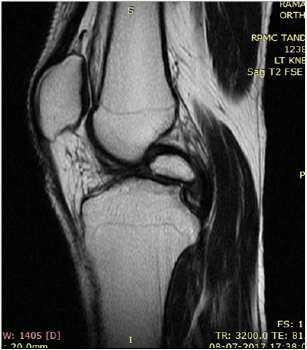

Figure 4: PD.

We present a case of 14 year old male child who had history of pain in the right knee while climbing upstairs for long duration. There was no history of any significant trauma in the past. After clinical examination by the orthopaedician in the outpatient department patient came to our department for MRI right knee with strong clinical suspicion of ACL injury. We did MRI of right of the patient and found a large ossicle intra-articularly which was impinging the ACL. The ossicle showed the signal intensity of bone on all pulse sequences. No other pathology was noted in the right knee joint (Figure 1-5).

An ossicle is defined as a mature lamellar and cancellous bone with a covering of hyaline cartilage and fatty marrow within. The aetiology of a meniscal ossicle has not been definitively established so far [1-3,6]. It has been suggested that it may have Congenital, traumatic and degenerative origins. The existence of intraarticular ossicles in knee is not very uncommon though however its occurrence to such a large size causing mass effect to ACL is rarely mentioned in the literature [5,6]. Rohilla et al. described a symptomatic meniscal ossicle in a 25-year-old male farmer which is also seen in our case [7]. Patients with such intra-articular ossicles present with pain and on X-ray are most commonly misdiagnosed as loose bodies however clinical signs and symptoms could easily distinguish the two entities as loose bodies seldom assumes such large size and cause symtoms [8,9]. MRI is helpful in depicting the nature of the mass by localizing its site and showing isointensity to the normal bone marrow in all pulse sequences. It is the most useful tool to differentiate it from loose bodies, chondrocalcinosis or osteochondritis dissecans [10]. It also rules out the existence or absence of any other pathology in the joint [11-14].